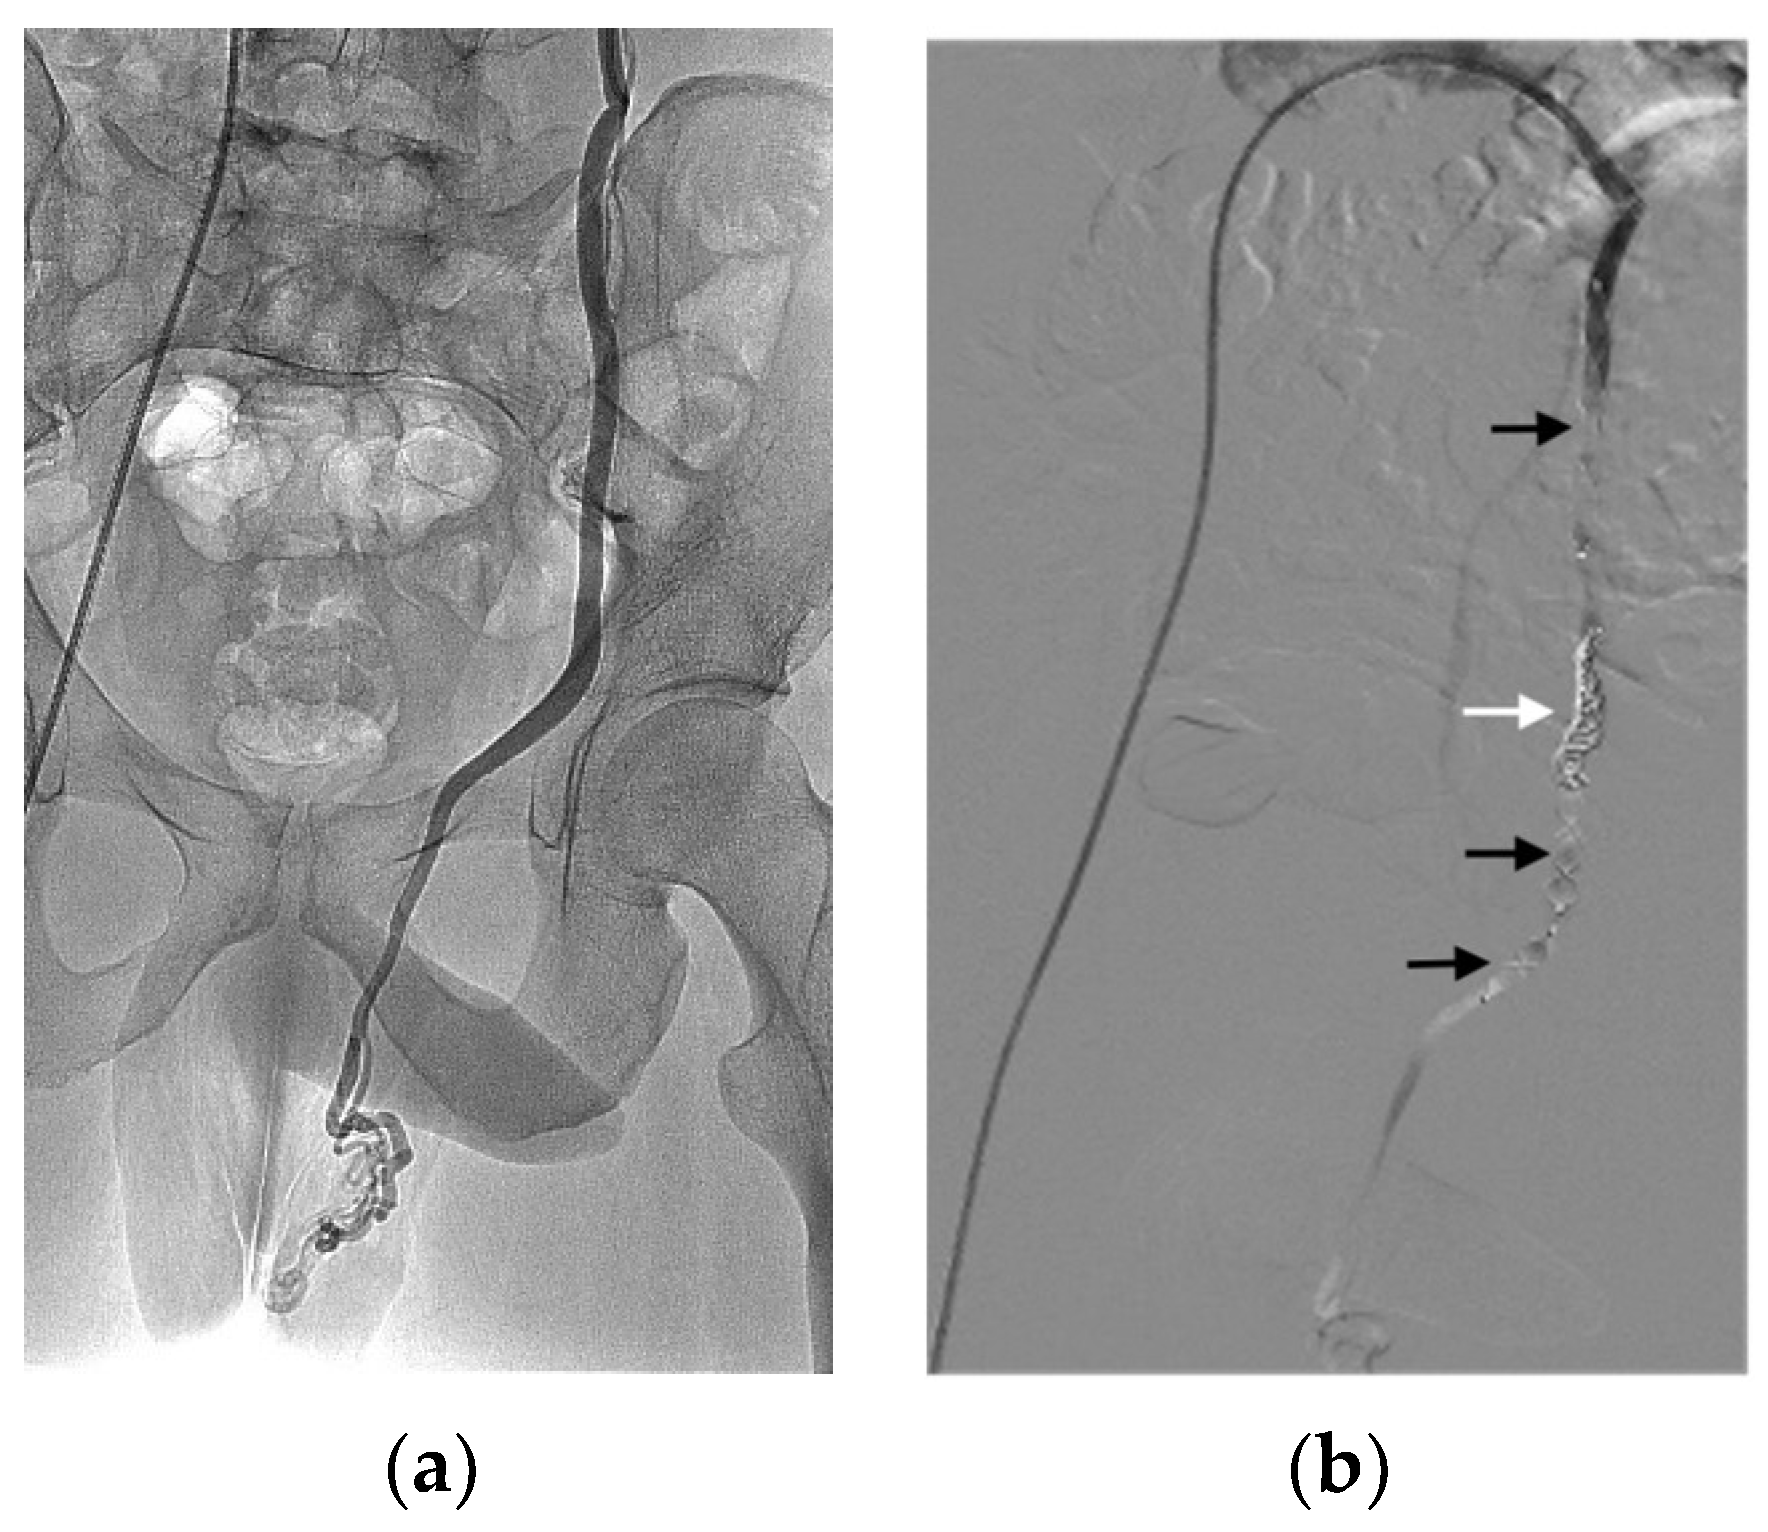

| Varicocele | 33 (29.8) |

| Haemostasis | 19 (17.1) |